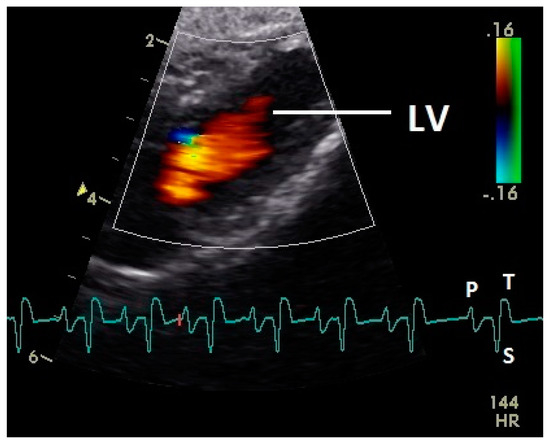

Figure 2.

Color Doppler image of the ventricle in mid diastolic phase. The vortex formation of the blood in the ventricle is visible (red and blue signal). LV: left ventricle; LA: left atrium; HR: heart rate. Electrocardiogram: P: P wave, S: S wave, T: T wave. The color scale on the right of the image is calibrated in m s−1.

Diastolic ventricular inflow was recorded in the atrium, across the AV valve and within the ventricular inlets and outlets. In the early diastole a red signal was recorded within the left atrium and across the mitral valve annulus into the left ventricle. This phase was interpreted as the passive ventricular filling due to left ventricular relaxation (descending part of T wave in ECG). Behind the longer septal part of the left AV valve leaflet and in the left outflow tract a blue signal in this phase of the cardiac cycle simultaneous to the red signal was observed in 42 birds (97.7%; Figure 1) and in the area of the lateral smaller parts of the left AV valve only in nine birds (20.9%; significant difference Chi-squared test p ≤ 0.001). In the mid diastolic phase in some pigeons the movement of the blood in the ventricle was observed (Figure 2). Within the P wave of the ECG an intense red blood flow signal was evident in the left atrium, crossing the left AV valve and entering the left ventricle as a sign of blood flow caused by atrial contraction. This rapid ventricular filling led to a visible blue signal in the left outflow tract, behind the septal part of the AV valve (97.7%), and in the some pigeons (48.8%; significant difference Chi-squared test p ≤ 0.001) also behind the smaller lateral leaflets of the left AV valve simultaneous to the red signal (Figure 3). In one pigeon the passive diastolic inflow was connected with the active ventricular filling (EA wave).

Constant simultaneous occurrences of red and blue color in the Doppler images of ventricles and atria show the presence of typical constant blood flow vortex formations in the avian heart, comparable to the mammalian heart [32]. Vortices in the cardiovascular system are supposed to play fundamental roles in normal physiology and provide a proper balance between blood motion and the stresses on the surrounding tissues [32]. In the color Doppler examinations of the pigeon heart in the “four-chamber view”, a vortex clockwise in the left atrium and counter-clockwise in the right atrium were observed. In this context the valva pulmonis of the left atrium is discussed as an important anatomical structure for sealing the atrial cavum [1]. However, the color Doppler images in our investigation show that in diastole (atrial contraction) and systole (atrial filling) the position of the valva pulmonis is very constant. There is no evidence for a motion of this valve which could contribute to the closure of the left atrium (see Figure 5, Figure 6 and Figure 7). The main function of this anatomical structure seems to be to direct blood flow towards the left ventricle (see Figure 6). The passive filling of the atria was visible after the P wave of the ECG as a cause of the relaxation of the myocardium and in the time of the end of the T wave of the ECG as a cause of the ventricular pump mechanism by the myocardial contraction in the systole. The findings in the color Doppler sonographic examination of the ventricles allow the conclusion of the presence of an asymmetric vortex ring in the left ventricle in the passive and active ventricular filling with a stronger vortex behind the longer septal part of the left AV valve (see Figure 1, Figure 2 and Figure 3). It is possible that an asymmetric valve shape allows a typical vortex formation (larger vortex in the direction of the outflow tract) that enables a faster blood flow and emptying of the ventricle [33]. Similar vortex formations in the left ventricle are described in the mammalian heart [32,33]. In the right ventricle the active ventricular filling leads to a great counter-clockwise blood vortex in this ventricle. The blood flow behind the right AV valve in the active ventricular filling as well as the active movement of this muscular valve during the closure seem to be important for the development of this blood flow vortex (see Figure 8). In connection with the asymmetrical shape of the right ventricle and oblique arrangement of the right AV valve [1], the shape of the blood vortex simplifies the outflow of blood through the pulmonary artery.